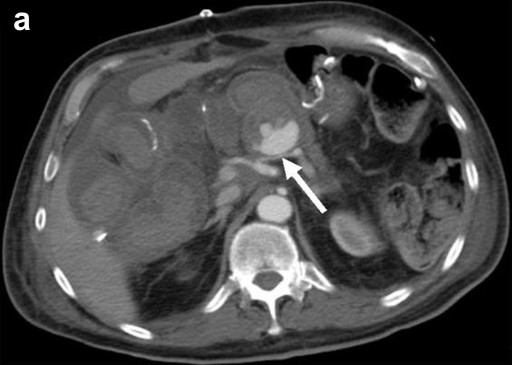

The sites of haemorrhage, management and outcome are summarised in Table 1. All PPH were classified by us as ISGPS type C. The initial CT angiogram revealed the source of the bleeding in all patients and 6 patients went on immediately to have mesenteric angiography. Stent grafting (n=2) was used to control bleeding sites in the common hepatic artery (Figure 1) and coil embolisation (n=5) was employed for bleeding sites arising from branches of superior mesenteric artery, gastroduodenal artery and splenic artery (Figure 2). One patient who underwent metal coil embolisation of proximal hepatic artery for a large psuedoaneurysm from the stump of gastroduodenal artery required further coil packing of the vessel and a follow-up CT scan two weeks after the initial embolisation demonstrated persistent flow in the common hepatic artery. No laparotomy was ever needed after embolization.

Figure 2. a. Axial CT image through the upper abdomen demonstrating a pseudoaneurysm arising from the proximal splenic artery. The splenic artery is compressed by pressure from extravasated blood at the site of the pseudoaneurysm neck (arrowed). b. Digitally subtracted angiographic image from the same patient showing occlusive embolisation coils placed in the splenic artery both distal to ("back door", straight arrow) and proximal to ("front door", curved arrow) the neck of the pseudoaneurysm. The tip of the catheter is in the coeliac trunk. |